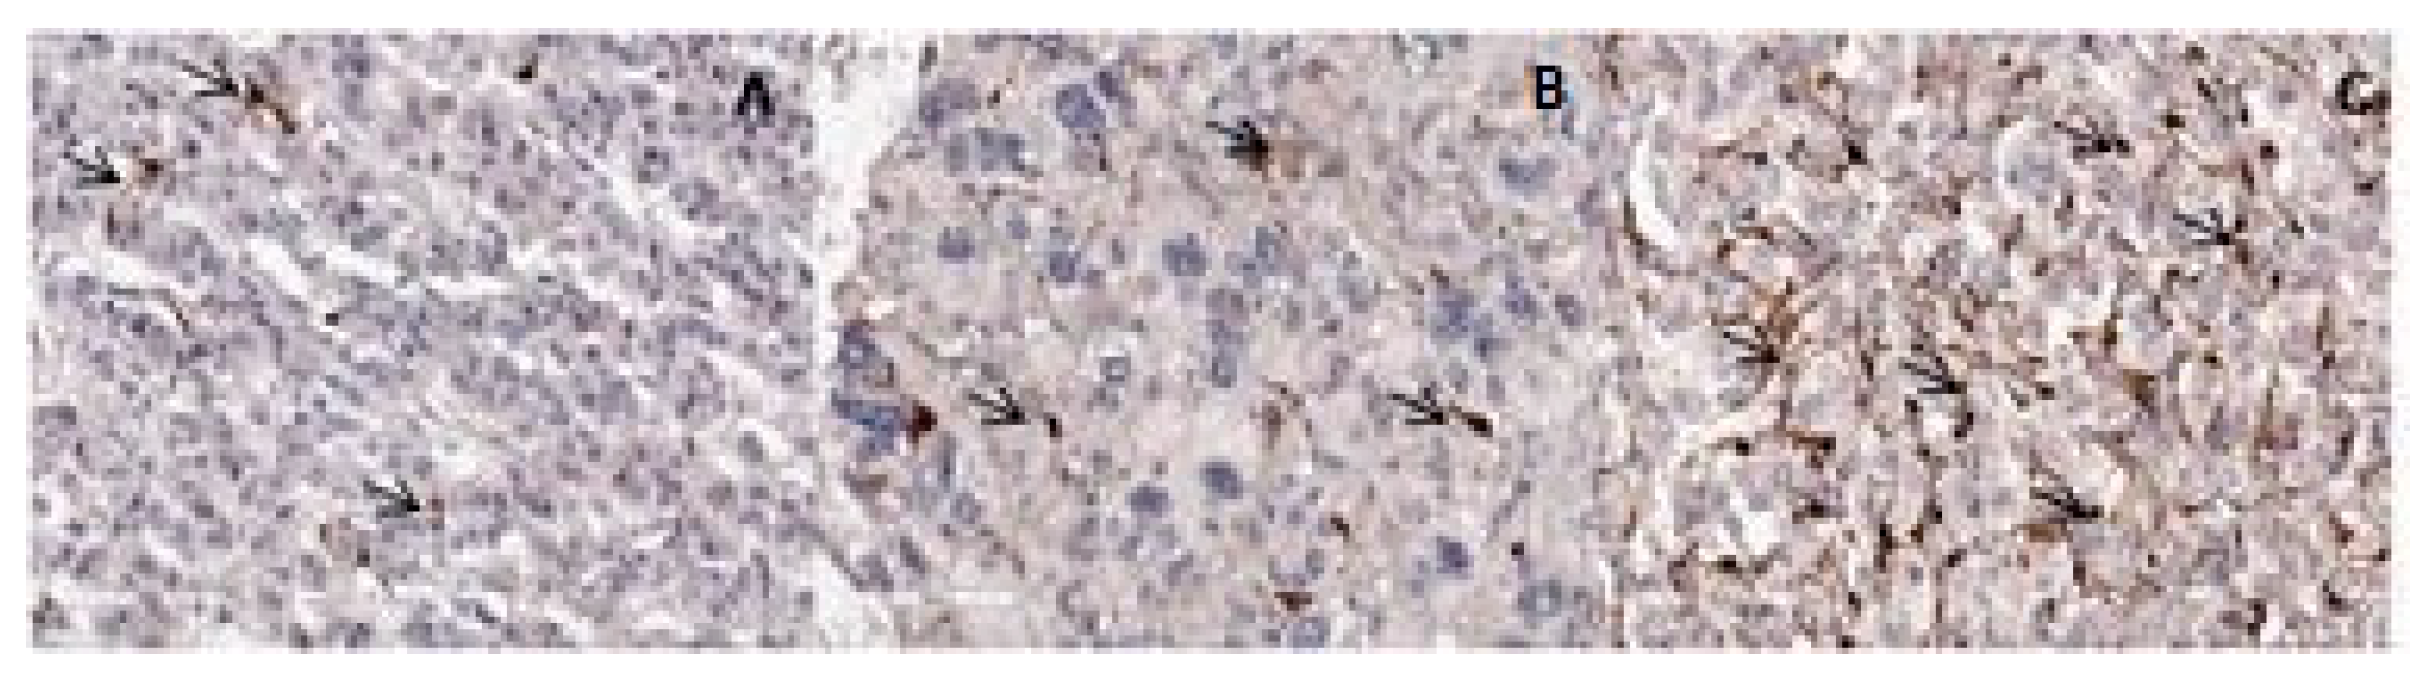

3.2. Microscopic and Immunohistochemical Findings